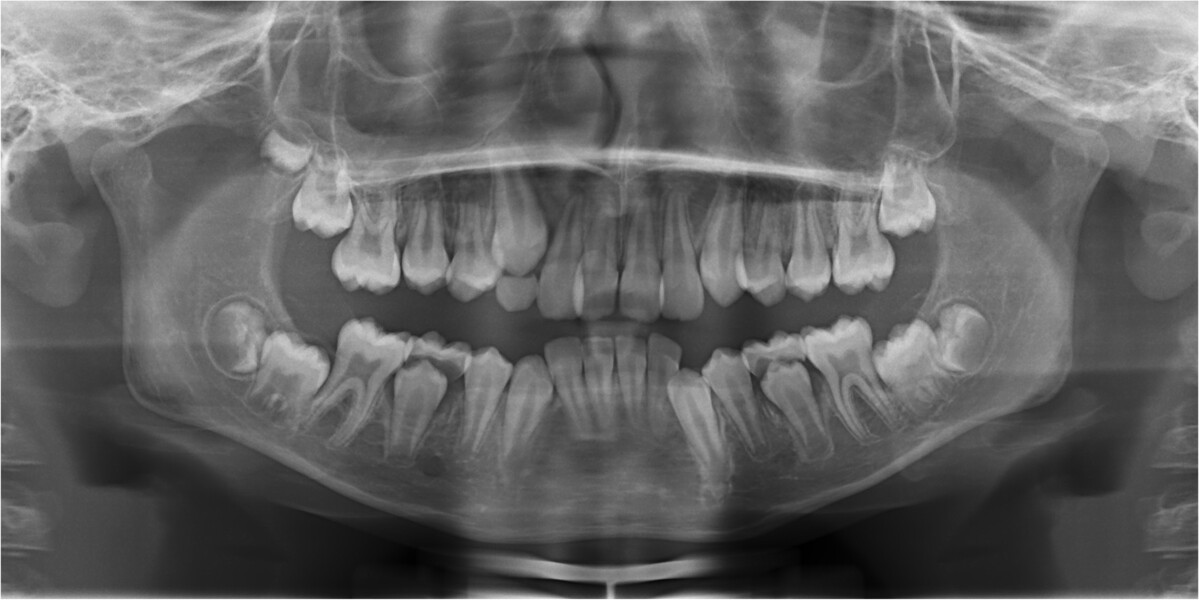

Fig. 3: Pretreatment panoramic radiograph.

Clinical and radiographic evaluation revealed (Figs. 1–3):

a bilateral full-cusp Class II molar relationship;

an increased overjet of 11.7 mm;

a traumatic overbite of 7.2 mm; and

a narrow, collapsed V-shaped maxillary arch with a 2.0 mm midline deviation to the right.

Cephalometric analysis confirmed a Class II skeletal pattern primarily caused by mandibular retrusion (ANB = 5°; SNB = 69°) and showed reduced mandibular length (94 mm versus a norm of approximately 110 mm; Fig. 4; Table 1). The vertical pattern was normo-divergent (SN/GoGn = 34°). Dentoalveolar analysis showed severe maxillary incisor proclination, pronounced crowding in both arches and an accentuated curve of Spee. Soft tissue analysis showed lower lip entrapment associated with the increased overjet, contributing to an unfavourable facial profile.